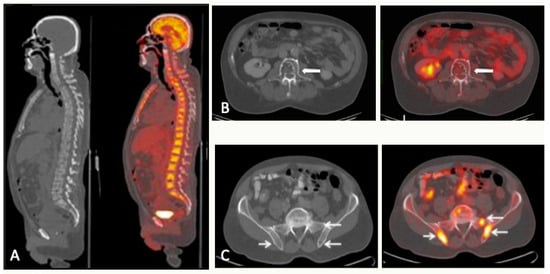

5. PET

5.1. PET/CT

5.1.1. Technique and Image Analysis

5.1.5. FDG-PET/CT vs. WBMRI